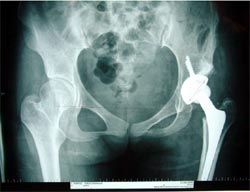

病例四

患者女性,34岁,左髋关节先天性脱位,股骨头坏死,疼痛明显,活动受限。采用生物固定全髋关节置换术,

髋臼予以加深后,用切除的自体股骨头植骨,髋臼稳定好。术后3年复查,假体没有松动,关节功能良好,没有疼痛。